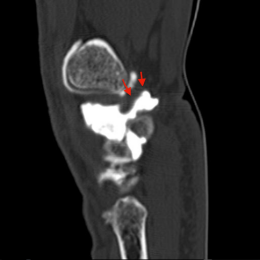

C et D - Arthro-scanner du poignet, vues sagittales : Visibilité du pédicule reliant le kyste a la cavité articulaire.

Kyste synovial de la face palmaire et ulnaire du poignet, issu de l'articulation piso-triquétrale.